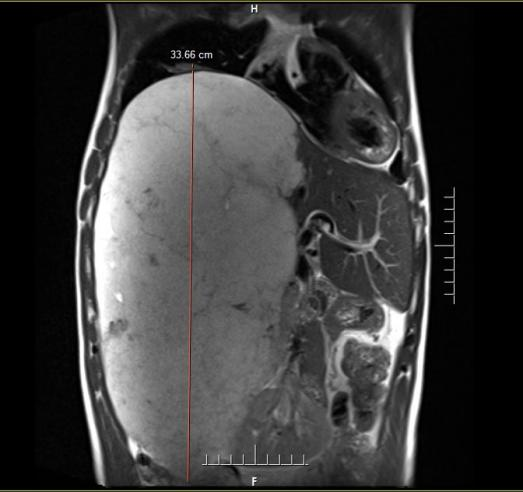

术前MRI提示肝脏巨大占位,纵向直径约34cm,直抵盆腔

李先生因持续上腹部不适前往该院就诊。影像学检查结果令医生和家属都大为震惊:其腹腔内存在一个巨大的占位性病灶,从上腹部一直向下延伸至盆腔,几乎占据了腹腔大量空间,并将右侧肾脏挤压至左侧。经诊断,这个巨大的占位被确认为肝血管瘤。